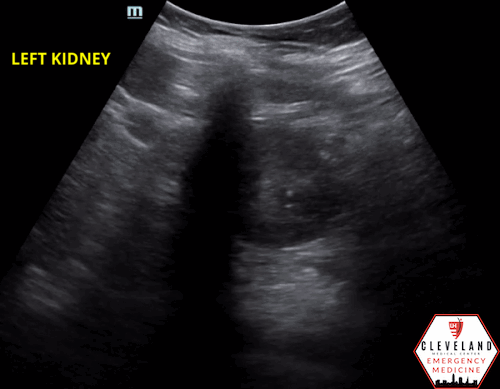

Renal POCUS was performed to evaluate for hydronephrosis and showed the following:

POCUS findings:

There is hydronephrosis of the left kidney. The right kidney is normal-appearing. Bladder views incidentally revealed a large complex, fluid-containing lesion in the pelvis (color doppler negative).